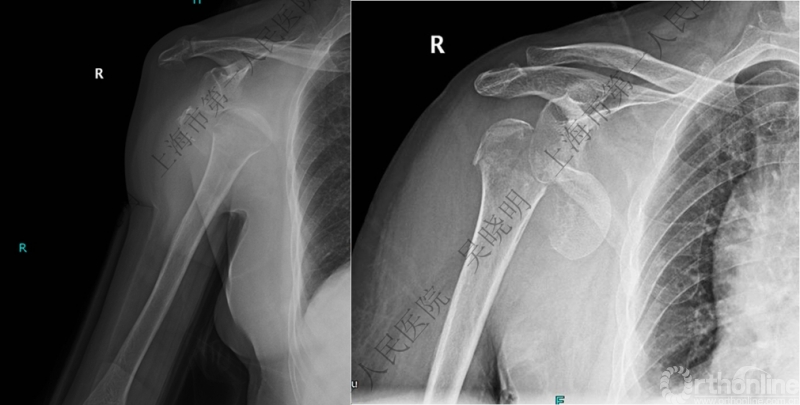

特别警惕伴肱骨头外翻合并大结节骨折的肩关节脱位

警惕:有无肱骨头外翻

伴大结节骨折的老年性肩关节前脱位伴肱骨头外翻

肩关节前脱位合并大结节骨折&肱骨头外翻:外翻压缩型(Neer 分型)

对这型骨折进行手法复位会导致肱骨头和肱骨干之间的连续性消失。肱骨头和肱骨干之间连续性尚存,肱骨头前脱位(Robsion 3b)